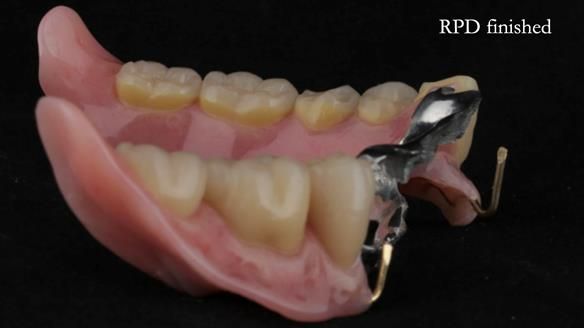

A metal-based upper RPD was made,

with metal backings incorporated to future-proof the design

should further teeth fail.

The way Rowan lengthened the teeth — particularly in the upper RPD — to match the existing gingival recession on the remaining teeth was superb. The dentures sit naturally within the context of the rest of the mouth.